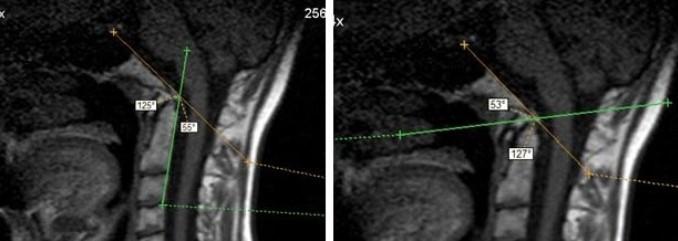

Аномалия Киари на снимке МРТ.